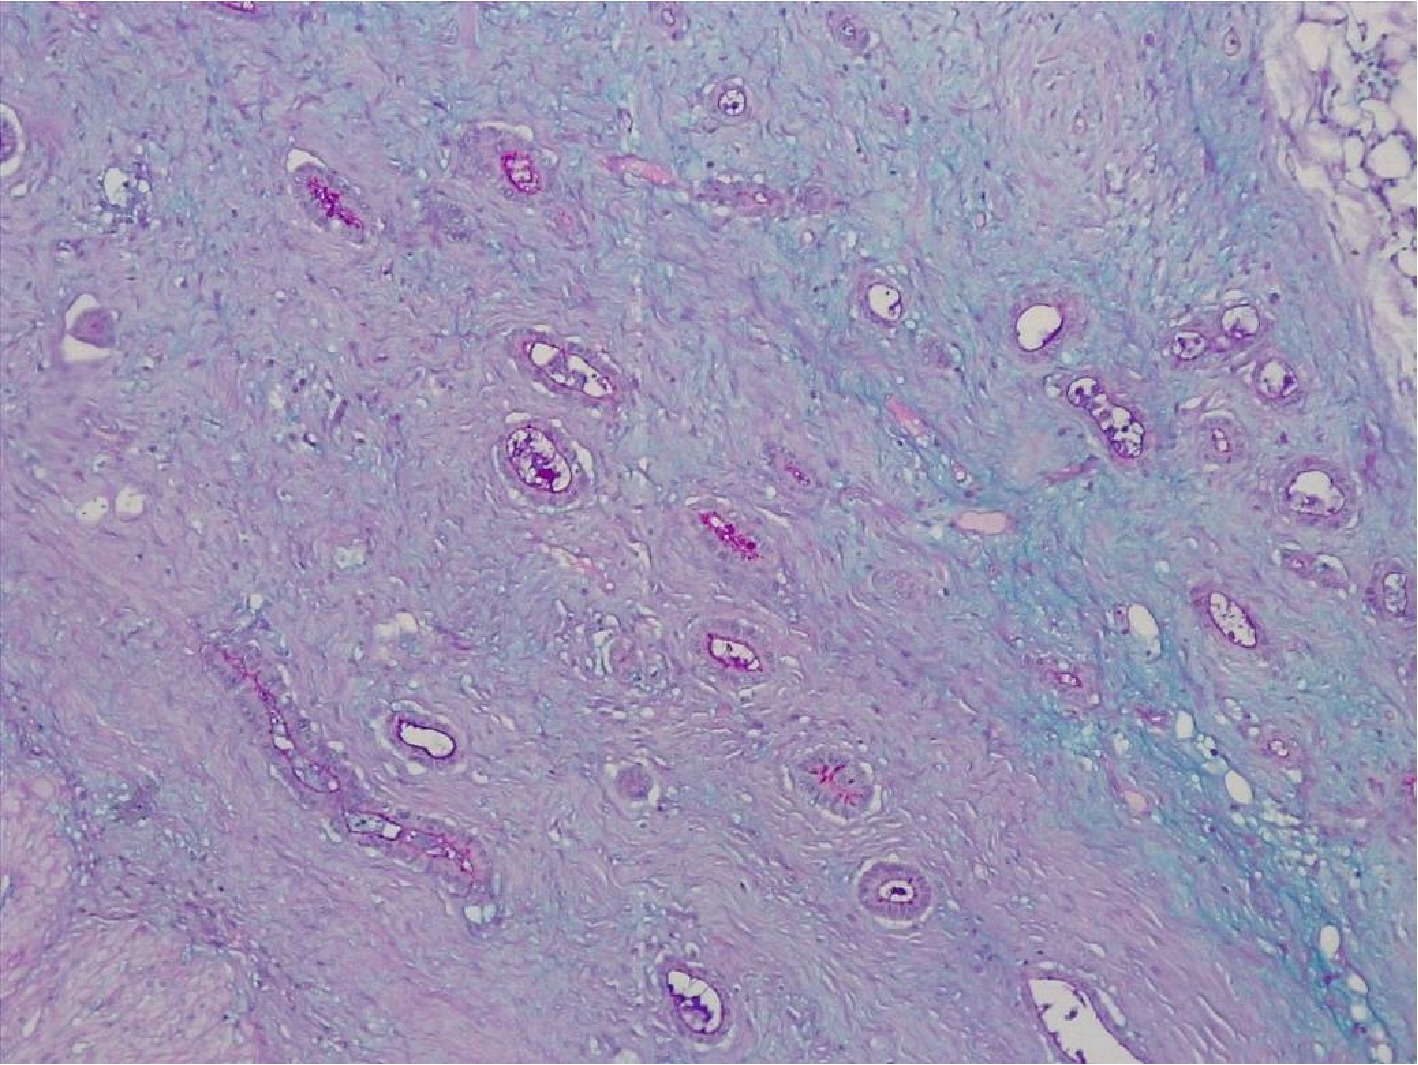

Для уточнения нейроэндокринного профайла карциномы были использованы антитела к хромогранину А и синаптофизину, которые выявили наличие нейроэндокринных гранул в цитоплазме части опухолевых клеток (рис.2).

Рис.2. Яркая экспрессия нейрон-специфической энолазы в цитоплазме опухолевых клеток тубулярной аденокарциномы. Иммуногистохимическое исследование с антителами к синаптофизину. Увеличение Х200.